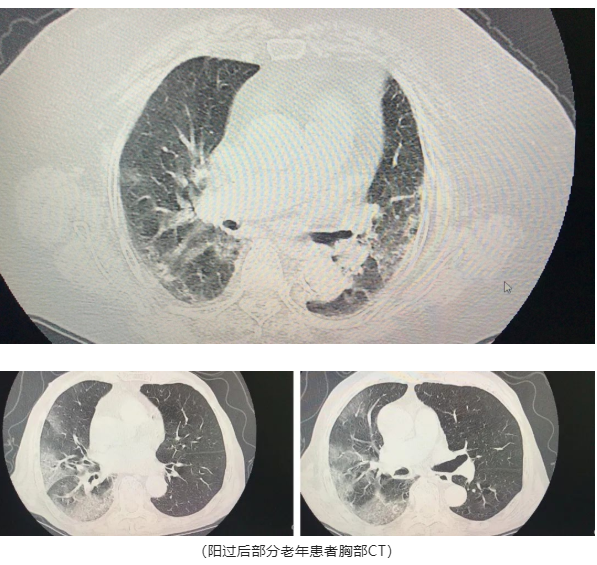

值得注意的是:节后,我院收治了多例新冠后肺炎患者,患者多数为有基础疾病的老年人,肺炎表现的相比年轻患者要严重的多,由于用药的特殊性及专业性和需要专业护理的条件,居家无法实现,因此此类患者建议还是要到院医治。

尤其对于老年人,在经历过新冠后的身体还未完全康复,肺部还很虚弱。呼吸道感染疾病很有可能发展成肺炎伴随其他疾病从而危及生命。因此关注老年人肺炎情况刻不容缓。